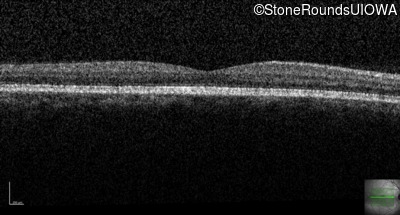

Congenital Stationary Synaptic Dysfunction (IA2g)

Congenital Stationary Synaptic Dysfunction (IA2g)

| Congenital Stationary Synaptic Dysfunction | CABP4 | Arg49Stop CGA>TGA | IVS1+1 G>T | AR |